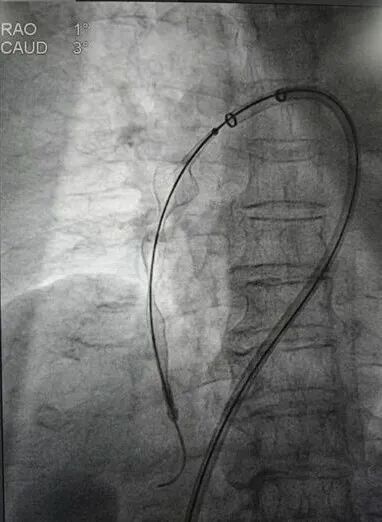

调整导丝至右下肺动脉,再次送入肺动脉取栓支架系统于右下肺动脉行取栓术,可取出较多暗红色血栓。复查造影提示右下肺动脉未见明显血栓,血流明显改善,测得肺动脉压力26/2mmHg。撤出血栓抽吸导管,于下腔静脉造影明确肾静脉位置腰1椎体下缘水平,在肾静脉位置以下成功置入下腔静脉可回收滤器,复查造影示下腔静脉可回收滤器位置正常。